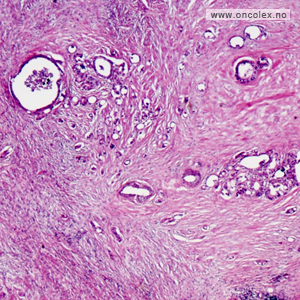

Tamkreft utvikles i mer enn 90% av tilfellene fra overflate-epitelet i slimhinnen som består av kjertler. Kreftsvulsten danner da unormale kjertelformasjoner og kalles adenokarsinom.

Bildeeksempler av svulst

Svulstens differensieringsgrad avhenger av hvor mye den avviker fra normalt vev:

- Lavgradig malign (tidligere kalt høyt til middels differensiert), svulsten avviker forholdsvis lite

- Høygradig malign (tidligere kalt lavt differensiert), svulsten avviker mye fra normalvev

Omtrent 20 % av adenokarsinomene er høygradig maligne og prognosen er da dårligere enn for de lavgradig maligne svulstene. Noen svulster produserer mye slim som ligger som sjøer mellom fast svulstvev, og kalles da «mucinøse»». Disse har også dårligere prognose.